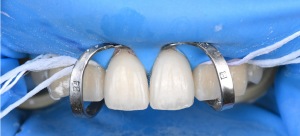

※歯面処理

ラミネートベニアを含むセラミック治療では、歯の表面にあるエナメル質にしっかり接着させることが重要とされています。

そのため、エナメル質の表面に専用の処理(エッチング)を行い、細かな凹凸を作ることで、接着力を高める工夫をしています。

※ラミネートベニア装着直後

エッチング処理のあと、歯とセラミックをしっかり接着させるための専用の薬剤(プライマー)を塗布し、レジン系の接着材を用いて装着しました。

このような接着の工程は、細かな手順と正確な操作が求められるため、十分な知識と技術が必要となる治療です。